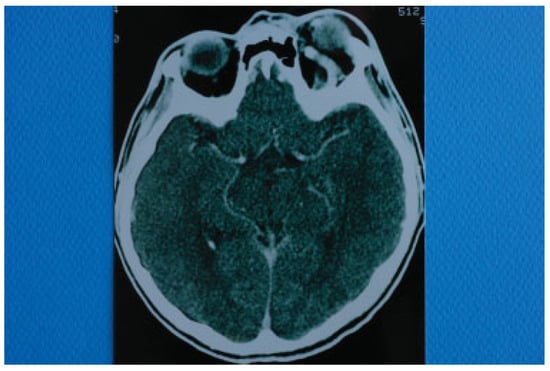

Figure 4. Computed tomography of the base of the skull illustrating a threefold dilation of the left cavernous sinus.

Two days after the removal of the foreign materials, there was a dramatic deterioration of the patient’s clinical presentation with intense ocular pain, worsening of exophthalmos, nausea, and vomiting. The patient also complained of “strange sounds in the cranium like water tapping.” Clinical examination revealed a systolic thrill on palpation of the left eye and a systolic wheeze on auscultation of the left frontal and temporal area. Measurement of intraocular pressure was subsequently performed and an intraocular pressure of 13 mm Hg in the right and 24 mm Hg in the left eye were recorded. Visual acuity was measured 5/6 vision and fundus examination revealed venous dilatation without further pathologic signs. The finding of intensive dilation of the left upper ophthalmic vein in the primary computed tomography was reevaluated and a posttraumatic CCF was suspected and included in the differential diagnosis. A new CT of the left orbit was ordered which revealed a threefold dilation of the cavernous sinus (Figure 4). The digital subtraction angiography (DSA) confirmed the diagnosis of CCF as it revealed a dilation of the cavernous sinus, a blood shunt between the lumen of the internal carotid artery and the cavity of the cavernous sinus, and a dilation of the upper ophthalmic vein (Figure 5).